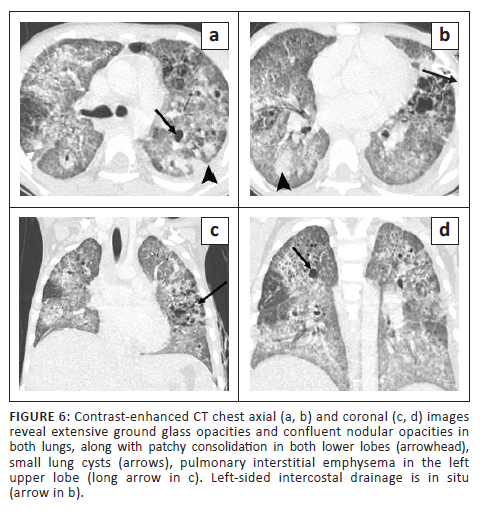

A 7-year-old girl was admitted with complaints of fever over 3 weeks, tachypnoea and cough for 4 days. In view of the respiratory distress, the child was transferred to the paediatric intensive care unit on day 5 post-admission. Mycobacterium tuberculosis was detected on sputum GeneXpert evaluation, and ATT was initiated. On day 11, the child experienced a sudden exacerbation of her respiratory distress. The CXR (not shown) revealed a left pneumothorax, for which an ICD was inserted. Subsequent CECT chest (Figure 6) revealed extensive GGOs and confluent nodular opacities in both lungs with patchy consolidation in both lower lobes, along with small cysts and bronchiolar dilatation. Other CT findings were mediastinal lymphadenopathy, pulmonary interstitial emphysema in the left upper lobe, minimal left pneumothorax with a pleural effusion, hepatosplenomegaly and hypodense non-calcified granulomas in the liver and spleen. The spleen also demonstrated a few small wedge-shaped regions of non-enhancing parenchyma suggestive of old infarcts. The patient responded well to ATT and recovered.

Most patients with tuberculosis who develop lung cysts have extensive bilateral infiltrative and exudative disease as a result of the pneumonic process.1,4,7 All the described cases had disseminated TB (with involvement of two or more noncontiguous sites), along with diffuse, bilateral lung involvement. These cystic lung lesions are often associated with centrilobular nodules and branching opacities in surrounding areas.2,3,6 Antibiotics were administered in all five cases, and none showed superadded bacterial infection. Three cases revealed numerous nodules, GGOs and consolidations. In Case 2, two CT studies were performed 2 months apart, which demonstrated a reduction in the lung nodules on treatment, with a corresponding increase in the number of cysts. Two cases showed predominantly cystic changes, with only a few nodules. One of these (Case 5) had received 5 months of ATT for MDR TB. In the presented cases, the cystic lesions developed during isoniazid treatment, rather than before or after treatment. This is in contrast to previous literature that describes certain instances of patients developing cystic lung lesions after isoniazid treatment.7

Tuberculous cysts are prone to rupture, leading to the development of recurrent pneumothoraces or pneumomediastinum.1,2,7,9 Pneumothorax was seen in four of the cases, likely as a result of cyst rupture. However, in Case 1, both cyst rupture and additional mechanical ventilation possibly played a role in the development of pulmonary interstitial emphysema and pneumomediastinum, which is difficult to differentiate radiologically.